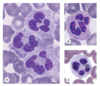

Neutrophils

What is their function?

Physical description?

What does polymorphonuclear mean?

Recognize & bind to Bacteria, foreign organisms, and infectious agents; Acute inflammation & tissue injury

Multi-lobed nucleus with lack of cytoplasmic staining

Varying shapes of nucleus

Eosinophils

Description of nucleus and cytoplasm?

What would cause increased counts?

- Bi-Lobed nuclei, Cytoplasm stains pink/red

- Increased counts with allergies and/or parasitic infection

Basophils

Nucleus?

- Lobed nucleus usually obscured by granules

Lymphocytes: Functional Cells of Immune System

Description of nucleus & cytoplasm

- Spherical nucleus w/ thin, pale blue rim of cytoplasm

Monocytes: Largest WBC

Description of nucleus?

- Heart/Kidney shaped nucleus